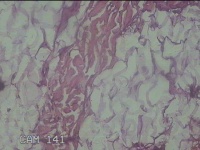

右侧颜面部结节

性别

男

年龄

49岁

临床诊断

皮脂腺囊肿

一般病史

发现右侧颜面部结节5年余。

标本名称

大体所见

灰白暗红色组织1x0.7x0.3cm一块,表面带梭形皮肤1x0.5cm,皮下见结节0.9x0.7x0.3cm一个,切开结节呈实性,切面灰白暗红色,质中。